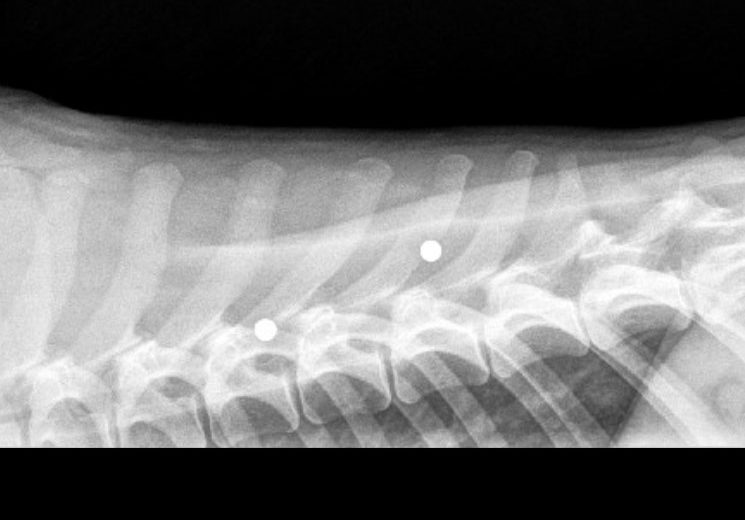

After looking closer at her medical records, we also learned that she had 2 BB pellets near her spine adding to concerns about her overall condition. Despite everything she had been through, Waffles remained incredibly sweet and friendly, just needing a little time to warm up to new people. Waffles entered foster care in August and had corrective surgery on both knees in September. Recovery has not been her favorite thing, but she has had an incredibly patient foster (and a lot of treats!) to get her through. After just three months of recovery, she is now walking so much better and enjoying life in her foster home!

• Tragically discovered BB pellets near her spine on X-rays